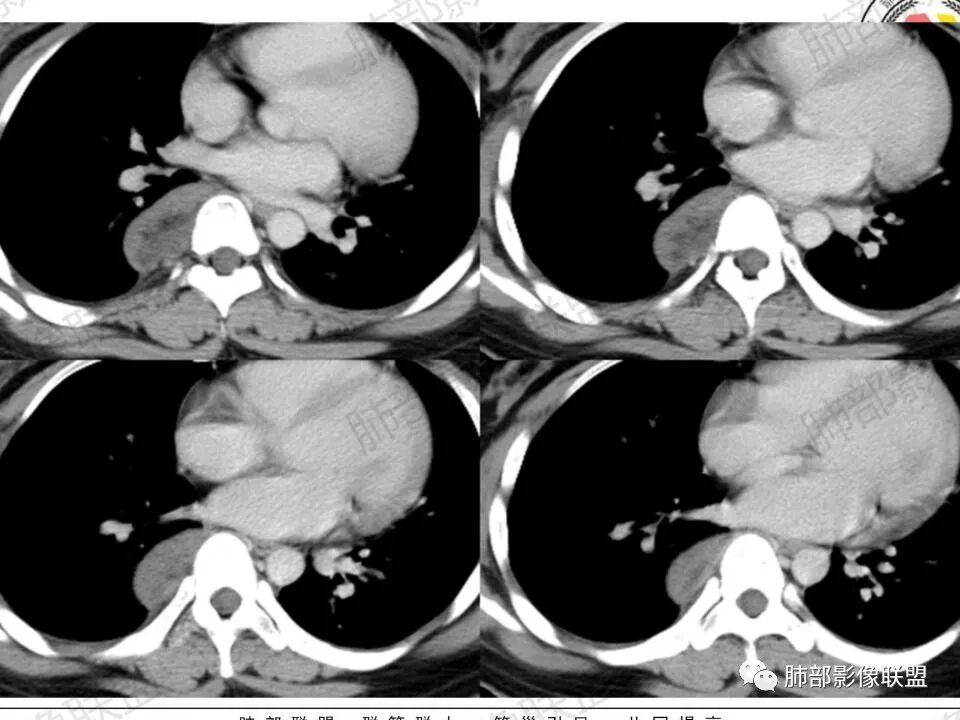

2.右后纵隔脊柱旁上下方向贴伏块影,“肾”形外观,边界清晰,密度不均,中央区域见脂肪密度影引向椎体前方,未见液性密度管腔影及钙化。

3.块影血供动脉来自肋间动脉,且由内后方侧入,其与下腔静脉之间未见回流通道。血管未见破坏,相邻组织未见侵入。

4.块影未延伸至椎管内,未见椎间孔扩大或骨质吸收破坏。

5.轻度渐进性强化。

2.肿块含脂肪等成分,与交感神经路径相一致,渐进性轻度强化(可能含有粘液成分)等,以节细胞神经瘤最可能!尽管未显示“习惯性”的钙化。

瘤体体积常较大,大部分有完整包膜,边界清楚,可沿周围组织间隙嵌入性生长,由于肿瘤质地较软,使得肿瘤可呈多种形态,其易沿着周围组织间隙生长、包饶,但不挤压周围器官或组织,邻近血管被包绕或穿行,呈嵌入式或铸型生长方式,这是后纵隔神经节细胞瘤的特征性表现;

后纵隔神经节细胞瘤常动脉期无明显強化、或轻度间隔、包膜或瘤体强化,延迟期可进一步斑片、结节状轻度或中度强化,强化程度进行增加,呈渐进性延迟强化,但強化程度一般为轻度到中度强化,究其原因可能是神经节细胞瘤瘤体内含有大量黏液基质和胶原纤维,使得细胞外间隙扩大,阻碍了对比剂的灌注,从而延缓了对比剂的积累,因此其动脉期多无明显强化或仅有轻度强化,延迟期呈渐进性轻度强化是后纵隔神经节细胞瘤强化特征。大部分病灶有轻度-中度强化,部分病灶无强化,这还可能与瘤组织内部间质血管含量多少相关,无强化病例瘤组织内部主要由胶质纤维和节细胞组成,间质血管较少,因此强化较低,而强化程度较高的病理可见较多的扩张、充血的毛细血管,引起较多的对比剂积蓄,因此强化相对明显。因此,神经节细胞瘤极少出现瘤组织早期强化,而多呈延长渐进性强化,增强扫描神经节细胞瘤内细胞成分可增强,黏液基质不强化。